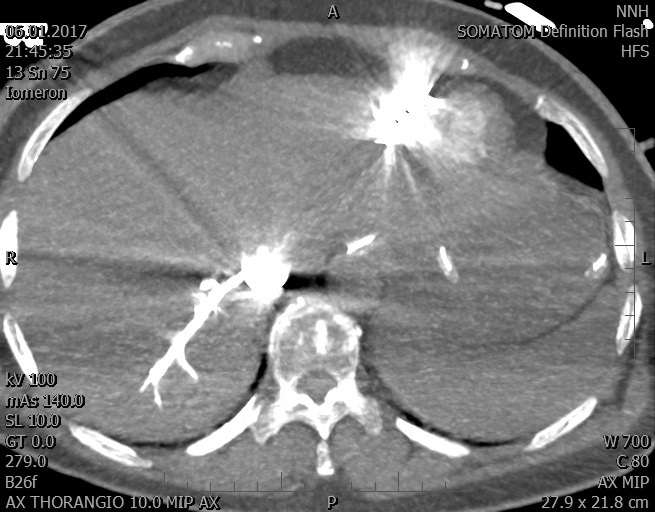

Video 2 - Echokardiograficky byla zjištěna těžká dysfunkce dilatační levé komory s nezvětšenou pravou komorou.Pro nejasnou příčinu zástavy jsme provedli i vyšetření výpočetní tomografií (CT), které vyloučilo plicní embolizaci (série 1 - soubory na konci článku). V den přijetí při přetrvávající oběhové nestabilitě byla nemocná opakovaně defibrilována pro fibrilaci komor se stabilizací rytmu po podání amiodaronu a mesocainu. Dle hemodynamických měření se jednalo o těžký kombinovaný šok. Vstupní laboratorní vyšetření bylo bez větších pozoruhodností. Posléze jsme doplnili anamnézu od příbuzných a zjistili, že pacientka užila do dvou hodin před srdeční zástavou první tabletu amoxicilinu na lehký respirační infekt. Při nevýtěžnosti vstupních vyšetření a nových anamnestických informacích jsme doplnili 14 hodin po kolapsu vyšetření koncentrace tryptázy v séru, která byla extrémně zvýšena (tabulka 2), což nás vedlo k podezření na anafylaxi.